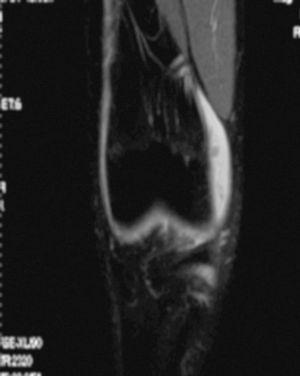

L'RM mostra (figs. 1, 3 i 5):

Figura 5 RM. Imatge potenciada en T1. Cossos lliures al voltant dels lligaments encreuats i en altres localitzacions intraarticulars.

• Múltiples cossos lliures intraarticulars.

• Lligaments i meniscos i resta d'estructures íntegres.